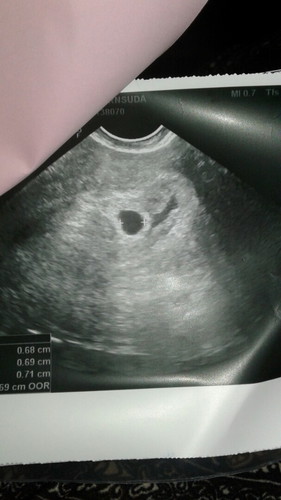

มดลูกบวม

แม่ๆท่านไหนท้องแล้วมดลูกบวมบ้างคะ แล้วมีผลต่อลูกในท้องไหมคะ ตอนนี้ซาวยังไม่เจอน้องเลยค่ะ หมอบอกเสี่ยงกับการแท้ง รกไม่สวย เป็นกังวลมากค่ะ อยากให้เขาอยู่ด้วย

คิดบวกก่อนค่ะคุณแม่ ตอนเรา 6 วีคไปซาว หมอก้บอกน้องตัวเล็กมาก เป็นจุดไข่ปลา รอติดตามก่อนนะคะ สู้ๆ คะ